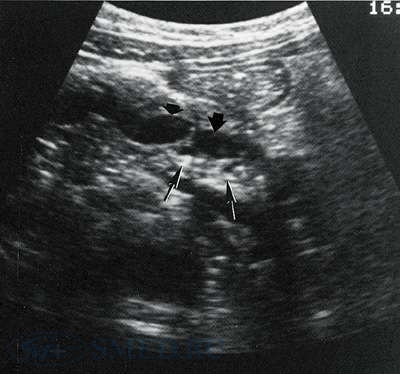

На УЗИ определяется форма, величина, особенности эхоструктуры, контуры, состояние панкреатических протоков, кист или опухолей, состояние внутри- и внепеченочных протоков. Значительным плюсом служит возможность проведения УЗИ-диагностики в динамике.